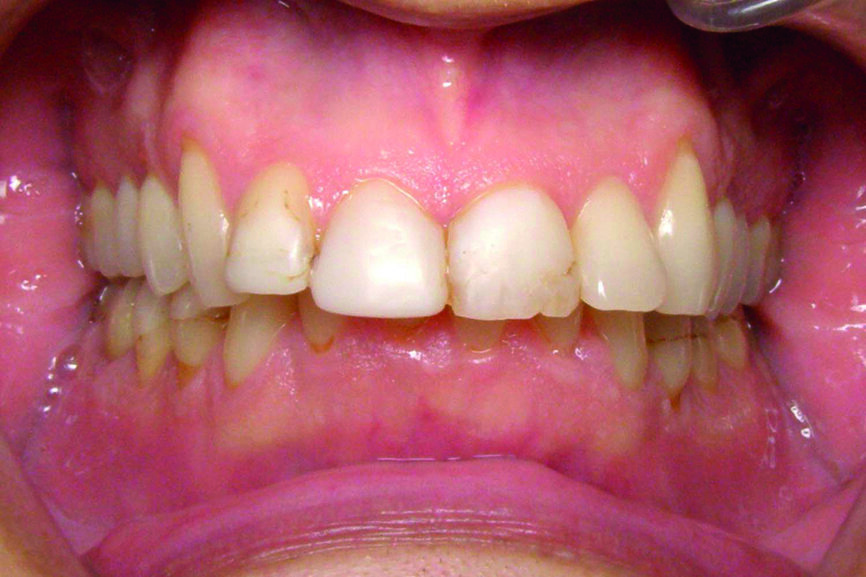

Le patient, 42 ans, s’est présenté au cabinet en 2018 pour connaître les solutions possibles pour améliorer son sourire. L’anamnèse révèle que le patient est gêné par la hauteur « raccourcie » de ses incisives mandibulaires, il a peur de les voir « disparaître » à moyen terme. L’examen clinique met en évidence :

- Une surocclusion importante ;

- des facettes d’usure sur les tables occlusales ;

- un bruxisme important, associé à une perte de la dimension verticale.

D’un point de vue dentaire le patient présente une Classe II division 1, avec une classe II molaire complète et une classe II canine.

- Présence d’un overjet et d’une supraclusion résiduelle.

- L’arcade supérieure est régulière mais les incisives sont en vestibulo version importante.

- L’arcade inférieure présente un encombrement dans le secteur antérieur associé à une version vestibulaire.